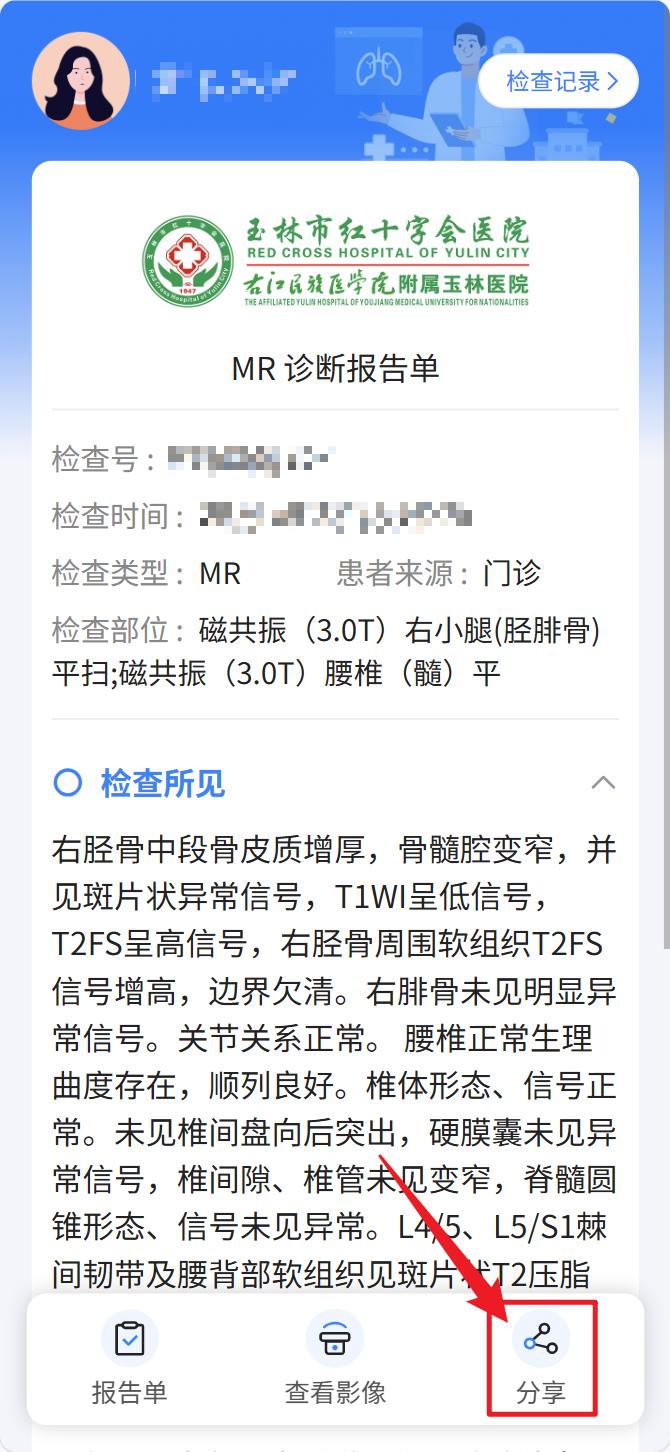

点击“报告单”和“查看影像”分别查看检查报告单及检查电子影像;

想分享给家人或医生?安排!点开云胶片,找到右下角的“分享”小图标,设置好有效期,生成链接或二维码,一键转发,对方就能安全查看~异地就诊、线上问诊,从此so easy!